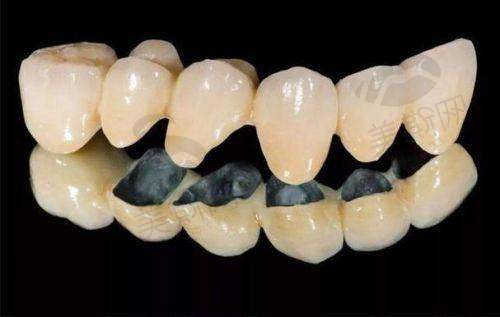

6. 口腔修复:提供全瓷牙冠、烤瓷牙、活动义齿等修复服务,运用数字化咬合重建技术,确保修复体与口腔组织贴合度达98%以上。

7. 武威市新怡然口腔医院全瓷牙冠(爱尔创):1280元/颗

8. 武威市新怡然口腔医院传统金属托槽矫正:8800元